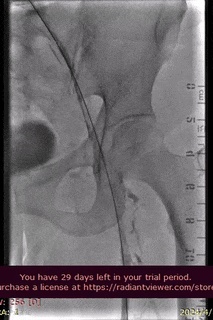

手术过程